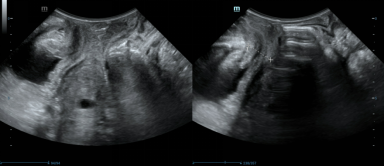

果不其然,张婷的盆腔影像学检查结果提示了很多结构异常。盆腔核磁检查结果显示:膀胱下段与宫颈之间粘连紧密,以前手术放入的网片与双侧三角区关系密切。盆底超声提示尿道旋转角及膀胱后角角度均有明显增大,尿道向后下方移位,但与尿道相连的膀胱上段却并无位置移动;在宫颈前方,7个月前手术放入的网片将子宫颈与膀胱后壁下段紧密粘连。这些信息,成为破解谜团,解除患者痛苦的重要线索。

“膀胱下段粘连固定,尿道却向后下方移位,因此尿道可能形成一定角度,阻碍排尿。”超声科专家耿京根据所见提出了推测。提供的动态超声视频显示,膀胱后壁上段与宫颈粘连固定在一起,并不与其他部位一起运动,这更加支持了该推测。